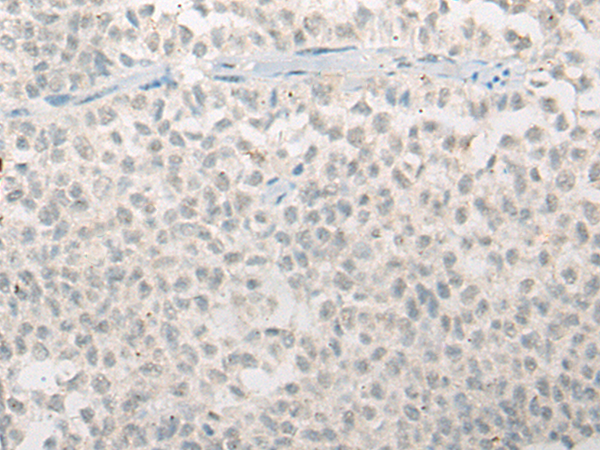

IHC positive control: |

Human esophagus cancer; Human ovarian cancer |